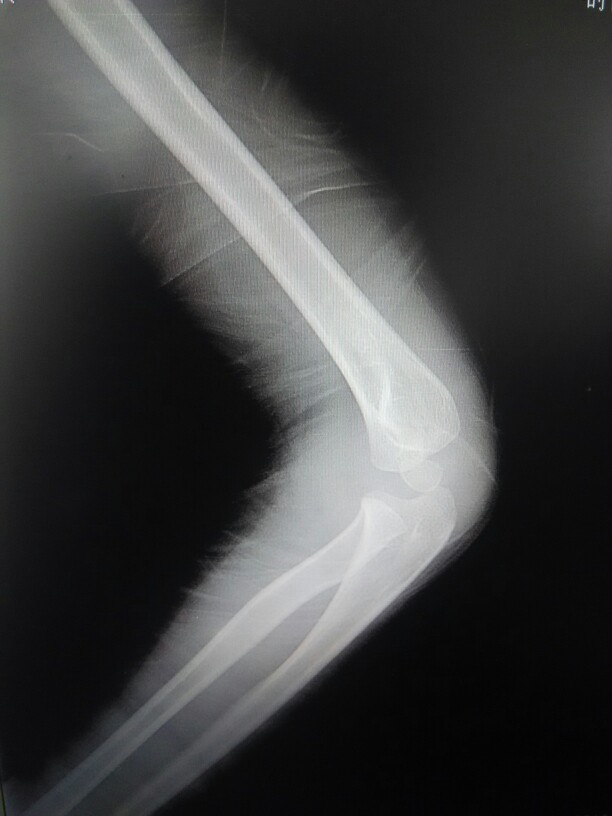

患者女,2岁,右肘关节摔伤后,肘关节肿胀,活动受限。照右肘关节正侧位片示:右肱骨远端关节面骨折,并肘关节脱位,关节囊肿胀。分析下小儿肘关节各骨及骨骺正常对合关系(如下线图)。

儿童6岁,肘关节外伤半小时,半小时前孩子在奔跑时无意中,摔伤右肘关节,来我院检查,如图,大家看一下有没有明显的,脱位骨折的情况。孩子一直说肘关节疼痛。那位骨科的老师,解释一下。